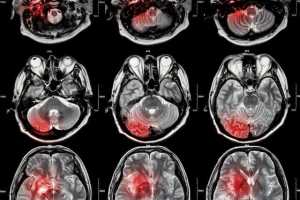

A descontinuidade de cuidados após a alta hospitalar está a comprometer a recuperação de pessoas que desenvolvem afasia na sequência de um acidente vascular cerebral (AVC). O alerta é do IPAFASIA – Instituto Português da Afasia, que defende a necessidade urgente de reforçar respostas estruturadas no pós-AVC e integrar a teleterapia como complemento regular de acompanhamento.

Em Portugal, estima-se que cerca de 40 mil pessoas vivam com afasia, condição que afeta a capacidade de comunicar, falar, compreender, ler ou escrever, frequentemente na sequência de um acidente vascular cerebral. Ainda assim, a resposta estruturada após a alta hospitalar permanece insuficiente.